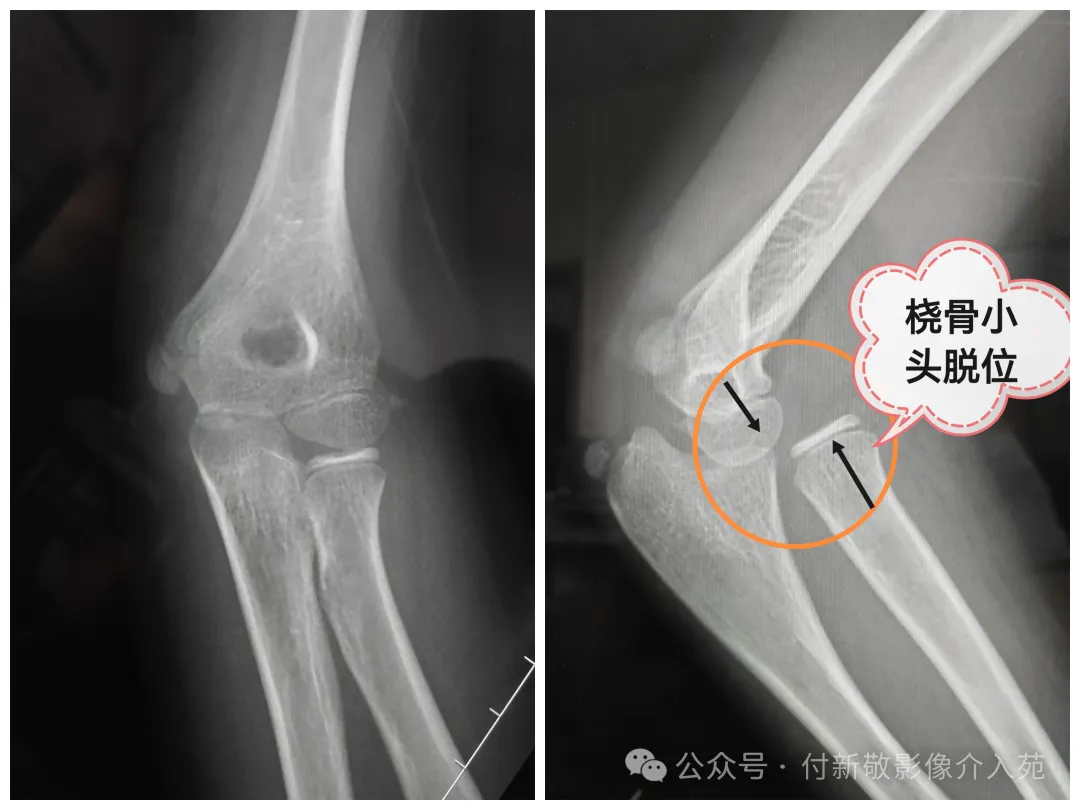

四、桡骨小头脱位

桡骨小头脱位和半脱位:多见于婴幼儿或少儿, 多因肘部外伤、用力牵拉上肢所致。患儿常哭闹不止,上肢拒绝活动,表现为无法正常伸曲和旋转前臂,疼痛及压痛明显。桡骨小头半脱位手法复位简单、高效,也是网络神医的摇篮。

肘关节X检查:桡骨小头半脱位在X线片上可表现为正常(因桡骨小头未完全脱出环状韧带)。桡骨小头完全脱位可明确显示肱桡关节对应关系异常,也可发现肘关节的骨折情况。